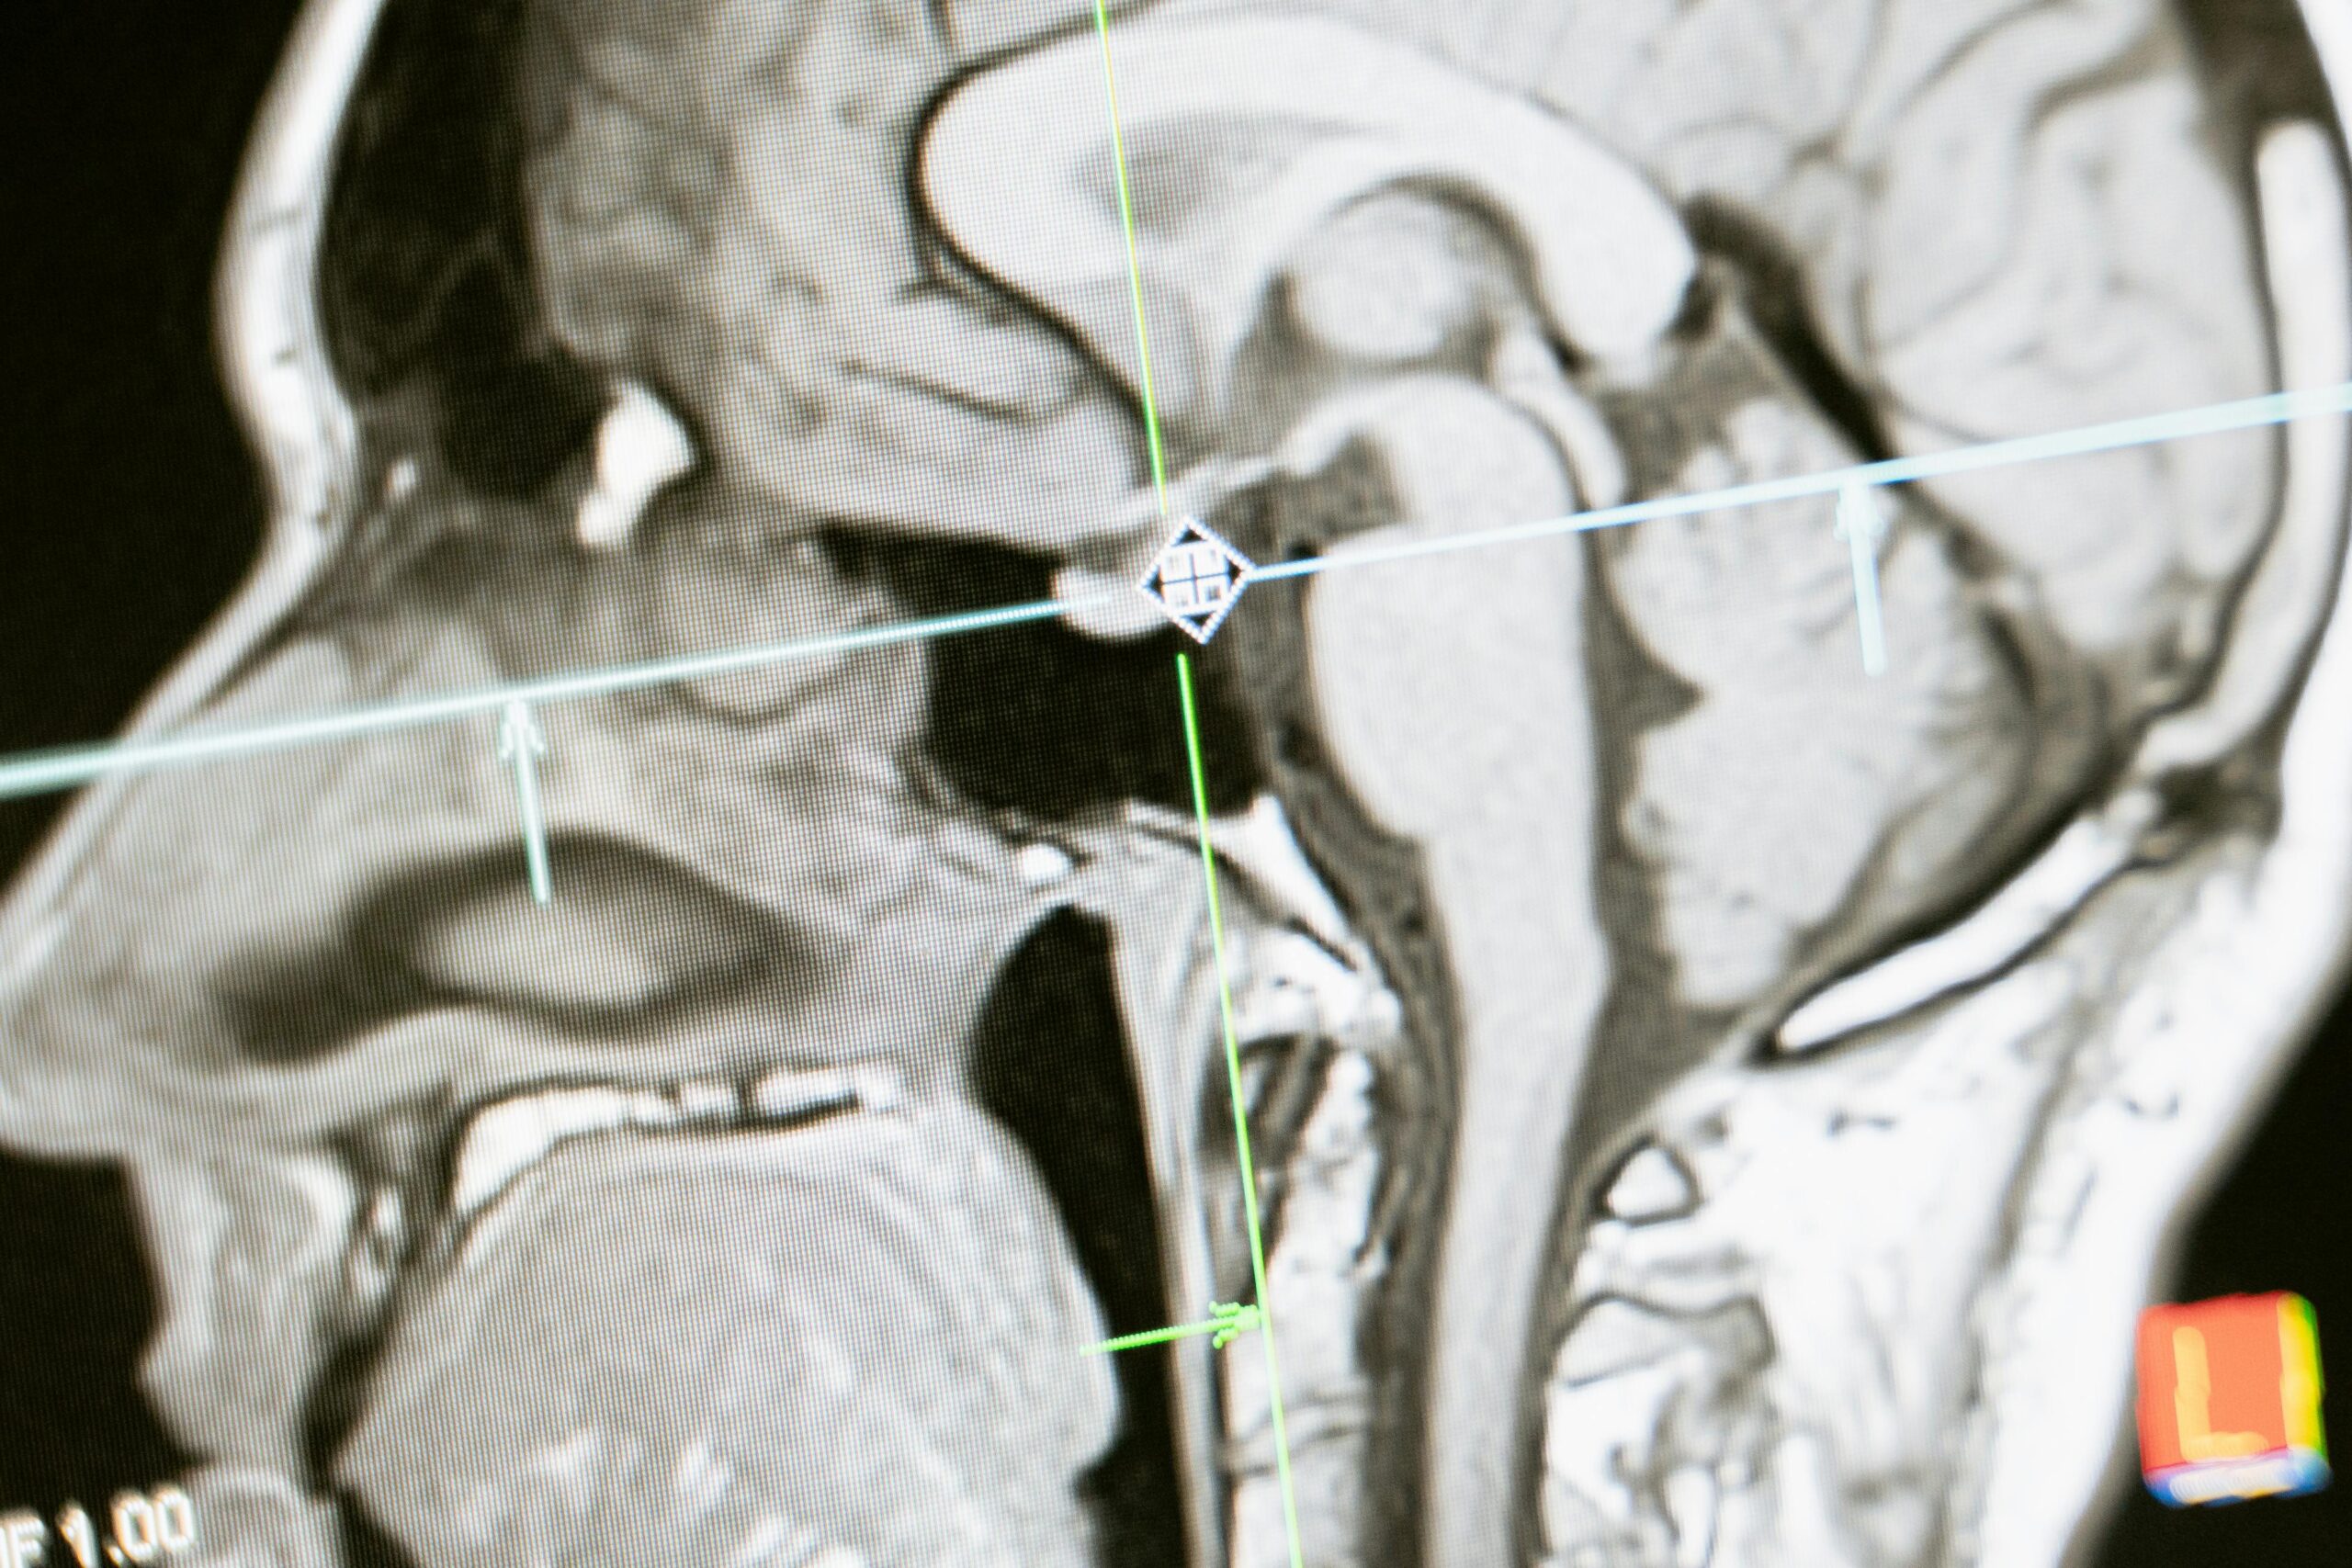

Diagnostic Imaging | ct

CT scans are often used to clarify an unusual or unexpected finding or to help discover the cause of symptoms a patient may be experiencing. The physician will usually order a CT scan for the section of the body that is of interest such as the head, neck, sinuses, spine, chest, abdomen, and/or pelvis. Repeat CT scans may be ordered to identify changes in the area of interest.